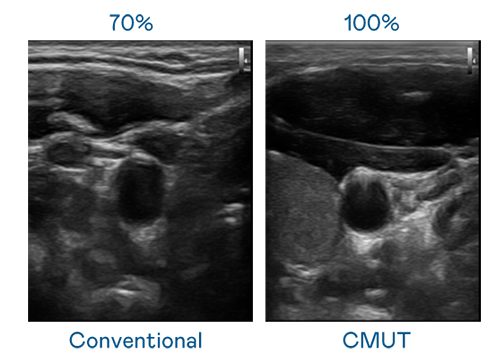

CMUT 技術是一種用電容式微機電元件來產生超音波訊號的技術。與傳統 PZT 壓電式技術相比,CMUT 頻寬增加 30%,更寬頻的超音波訊號讓影像解析度大幅提升,是實現高影像品質醫療超音波掃描、促進精準醫療發展的關鍵技術。

超音波影像的解析度高低,首先取決于探頭能發出的訊號頻寬。金世豪 CMUT 可提供高清晰的超音波訊號,提供高頻寬、高靈敏度、影像紋理細節更高的超音波影像,協助醫護人員縮短影像判讀時間及利用精準的醫療影像進行診斷。